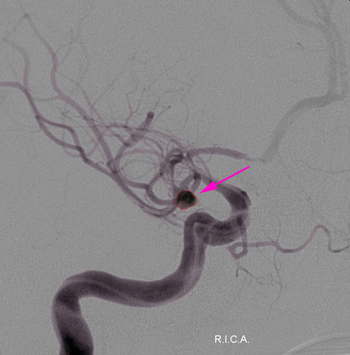

Αρτηριοφλεβώδης δυσπλασία (περίγραμμα). |